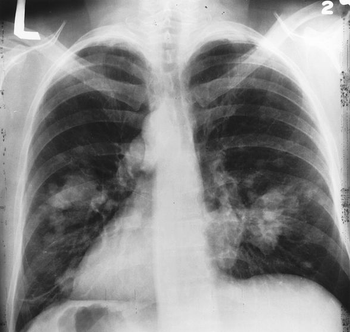

A novel agent that inhibits the PD-1/PD-L1 pathway showed good results in particular among smokers with non-small-cell lung cancer, a particularly promising result from a phase I trial.